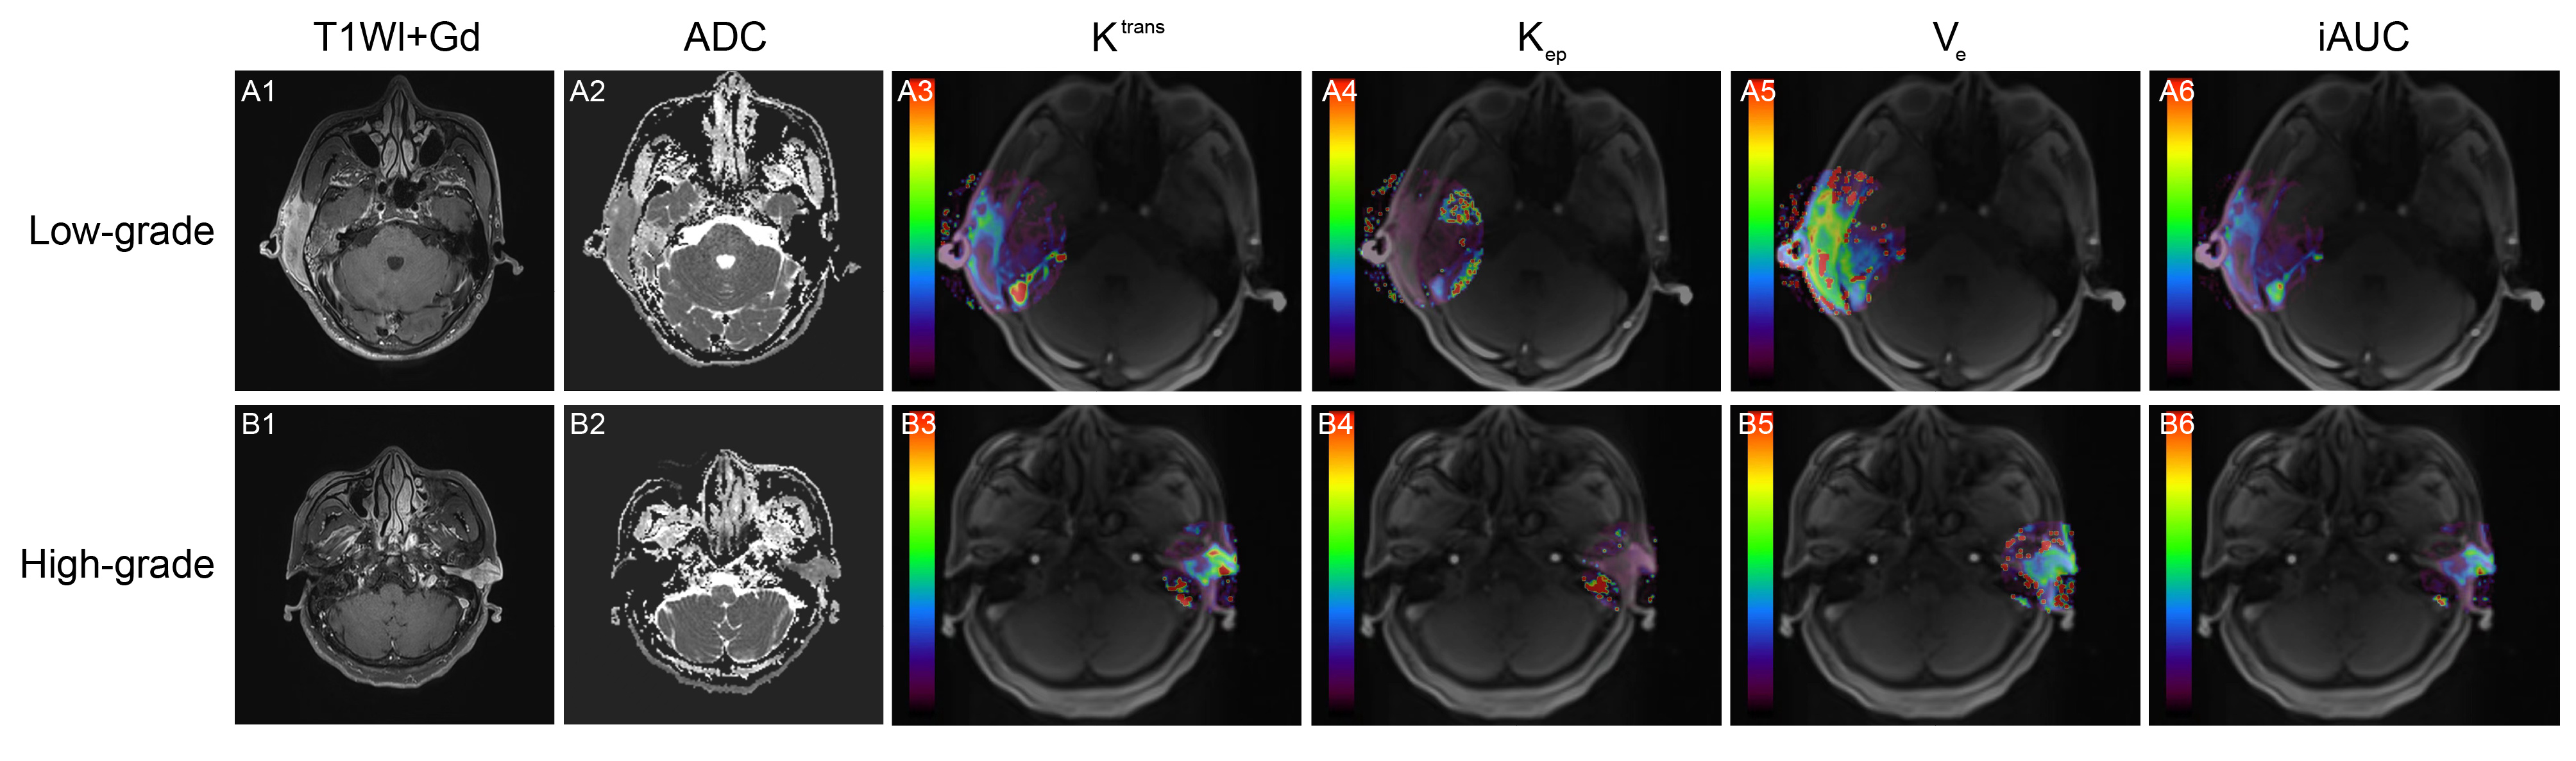

Methods: Retrospective diagnosis of 23 ear and temporal ACC patients was confirmed based on surgical pathology from March 2020 to April 2024. All patients underwent routine MRI, DWI, and DCE-MRI scans within one week before surgery. The lesion ADC values and DCE-MRI perfusion parameters, including Ve, Kep, Ktrans, and iAUC, were measured. Consistency tests were conducted on the measurements done by two physicians. The ADC values and DCE-MRI perfusion parameters between different pathological grades were compared. The correlation among all parameters and ACC pathological grading were analyzed, and the diagnostic accuracy of each parameter was assessed using receiver-operating-characteristic (ROC) curves.

Results: The measurements from the two observers showed high consistency (ICC > 0.9). Ktrans, iAUC, and ADC values demonstrated significant differences between different pathological grades (P < .01, P < .05, P < .05). Correlation analysis indicated that Ktrans, Kep, Ve, and iAUC were positively correlated with ACC pathological grading, and Ktrans demonstrated the most robust correlation (correlation coefficient r = .578, P < .01). In contrast, ADC values were markedly and negatively correlated with pathological grading (r=-.470, P < .05). In ROC analysis, the area-under-the-curve (AUC) for Ktrans, iAUC, and ADC were 0.841, 0.790, and 0.778, respectively, all higher than those for Kep and Ve. Ktrans showed the best diagnostic performance.